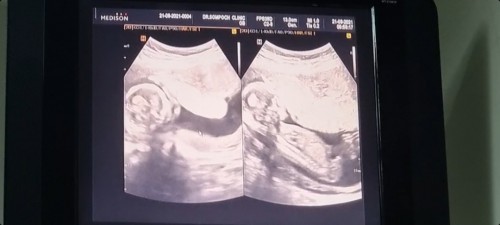

15w6d ผมเป็นผู้ชาย

หมอบอกน้องโอเคดี โตตามเกณฑ์ เห็นจู๋แล้ว ท้องแรกผู้ชายท้องสองก็ผู้ชาย แม่ยังคงเป็นหญิงเดียวในบ้าน😆